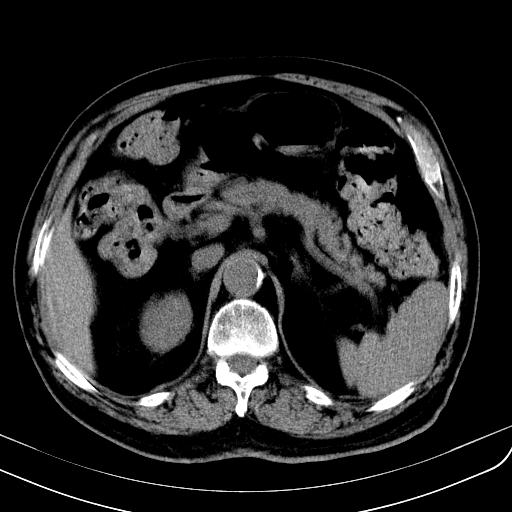

胃底靠近胃大弯处可见一圆形软组织影,直径为3.45cm,ct值约为30.1hu

请会诊!!!